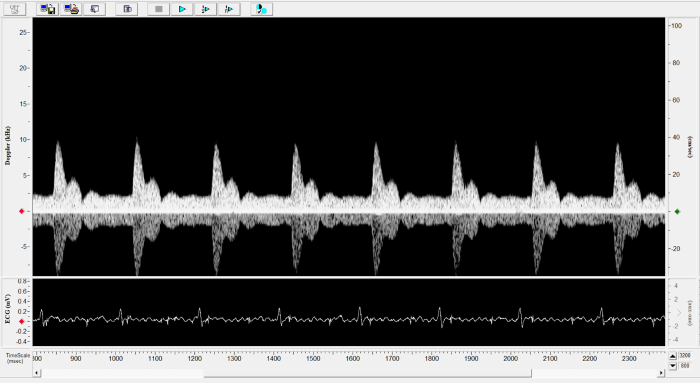

Imaging gallery - Doppler Flow Velocity System

Rat - Transverse Aorta. Image Credit: Scintica Instrumentation Inc.